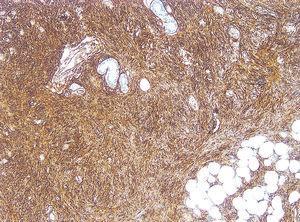

Fig. 4.--Intensa positividad para CD34.

El estudio inmunohistoquímico de las células tumorales fue negativo para el factor XIIIa e intensamente positivo para el marcador CD34.

La apariencia histopatológica típica del DFSP consiste en una densa proliferación de células fusiformes con núcleo abombado, dispuestas en haces arremolinados en un patrón estoriforme denominado en rueda de carro, alrededor de áreas acelulares centrales de tejido colágeno 4. Desde esta zona parten radialmente fascículos de células neoplásicas que invaden el tejido adiposo subcutáneo desde la dermis profunda, ya sea dejando islotes de adipocitos entre los fragmentos del tumor (patrón en panal de abejas, 30 % de los casos), ya sea en bandas paralelas a la epidermis (patrón en hojaldre, 60 % de los casos). Las células muestran grandes núcleos ligeramente pleomórficos, con escasas figuras mitóticas. En su periferia, el tumor tiende a crecer emitiendo prolongaciones mal delimitadas, lo que explica la dificultad clínica e histológica para determinar sus límites y la elevada tasa de recurrencia tras la extirpación quirúrgica convencional 8. El DFSP muestra positividad para CD34 y negatividad para factor XIIIa y proteína S-100, de gran valor para el diagnóstico diferencial con otros tumores.